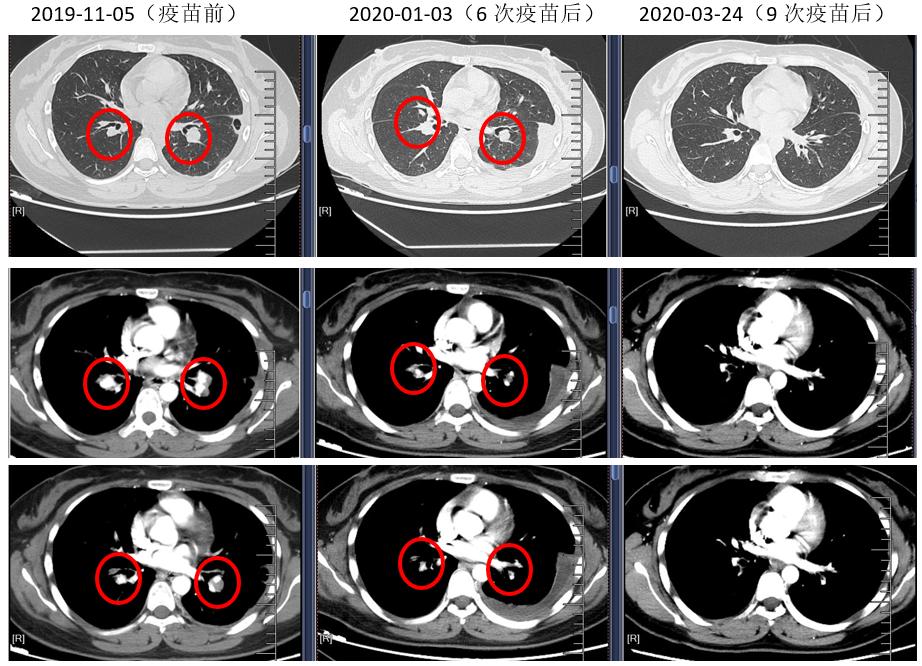

2019-11-05开始采用NY-ESO-1癌睾抗原肽纳米疫苗+抗PD-1抗体+安罗替尼综合免疫治疗模式。经过治疗后患者肺部病灶消失(CR),咳嗽症状缓解。

图一 免疫综合治疗前后影像学评估

这是一例年轻女性下肢滑膜肉瘤晚期病例,患者术后不到半年就出现肺部转移,单纯口服安罗替尼时肺部病灶略有缩小,咳嗽症状稍有缓解,疗效评价仍然为SD。我们将个体化癌睾抗原肽纳米疫苗和抗PD-1抗体加入进来,进行免疫治疗的综合模式,患者纵隔多个病灶逐渐退缩至完全缓解达CR。这名患者在治疗中期出现过左侧胸腔积液,治疗继续进行,后胸腔积液逐渐消失,考虑为反应性胸水。患者免疫组化检测NY-ESO-1 ++,我们基于癌睾抗原肽纳米疫苗和抗PD-1抗体的综合免疫治疗模式,为她带来了较好的治疗效果。